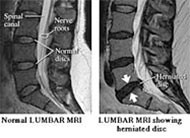

Εικόνα 2. Απεικόνιση κήλης μεσοσπονδυλίου δίσκου σε μαγνητική τομογραφία (MRI)

Η διάγνωση της κήλης τίθεται με ακρίβεια με τη μαγνητική τομογραφία (MRI), όμως και η απλή ακτινογραφία είναι χρήσιμη στη διαφοροδιάγνωση από άλλες καταστάσεις, όπως οι όγκοι, ενώ και η στένωση του μεσοσπονδυλίου διαστήματος στην ακτινογραφία είναι ένδειξη για πιθανή κήλη. Πάντως, δεν σημαίνει πως όποιος έχει κήλη θα πρέπει απαραιτήτως να πονάει ή να υποβληθεί σε κάποια θεραπεία, καθώς μεγάλο ποσοστό παραμένει ασυμπτωματικό ή ο πόνος εξαφανίζεται με την πάροδο του χρόνου.